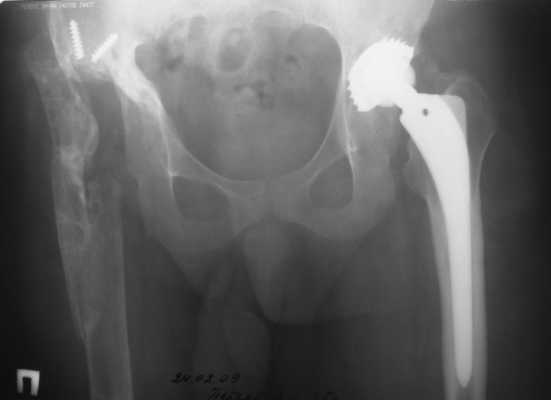

2003 г. нестабильность тазового компонента (рис. 2) - протез удален.